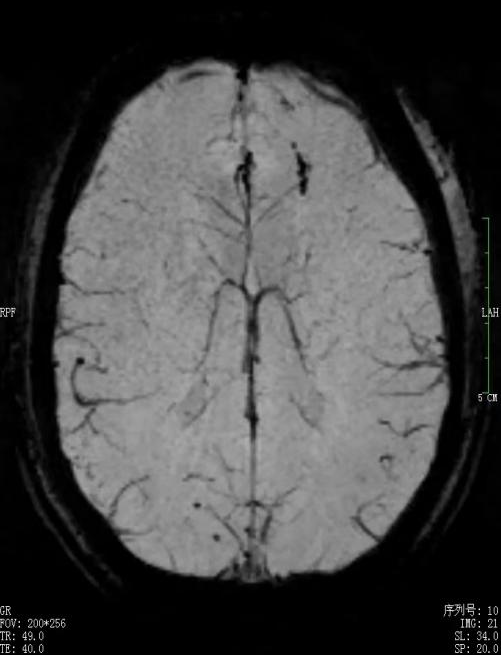

1.5T(左)3.0T(右)头颅磁敏感对比